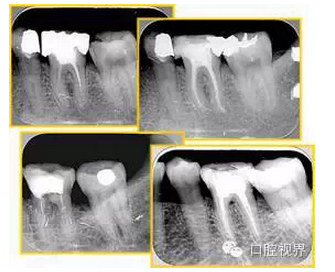

左圖為根管充填術(shù)后 X 線片。圖中可見(jiàn),根管充填較好。右下圖有白色小點(diǎn),為側(cè)方加壓導(dǎo)致糊劑擠出所致,表明根管充填比較致密。

多根牙時(shí)候需進(jìn)行偏移投照,正位投照無(wú)法說(shuō)明具體哪根牙根管充填效果。